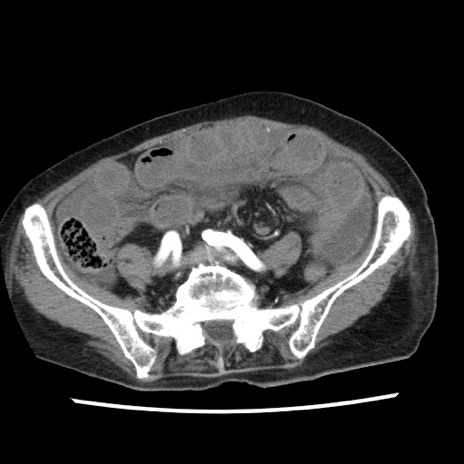

症例1(横断像)

【症例】80歳代女性

【主訴】腹痛

【現病歴】8時間前から腹痛あり来院。

【既往歴】糖尿病、脂質異常症、子宮体癌にて子宮全摘術

【身体所見】意識清明・会話良好だが腹痛で苦悶様、全腹部にわたって反跳痛と圧痛あり

【データ】WBC 13600、CRP 0.14、LDH 224、CK 90